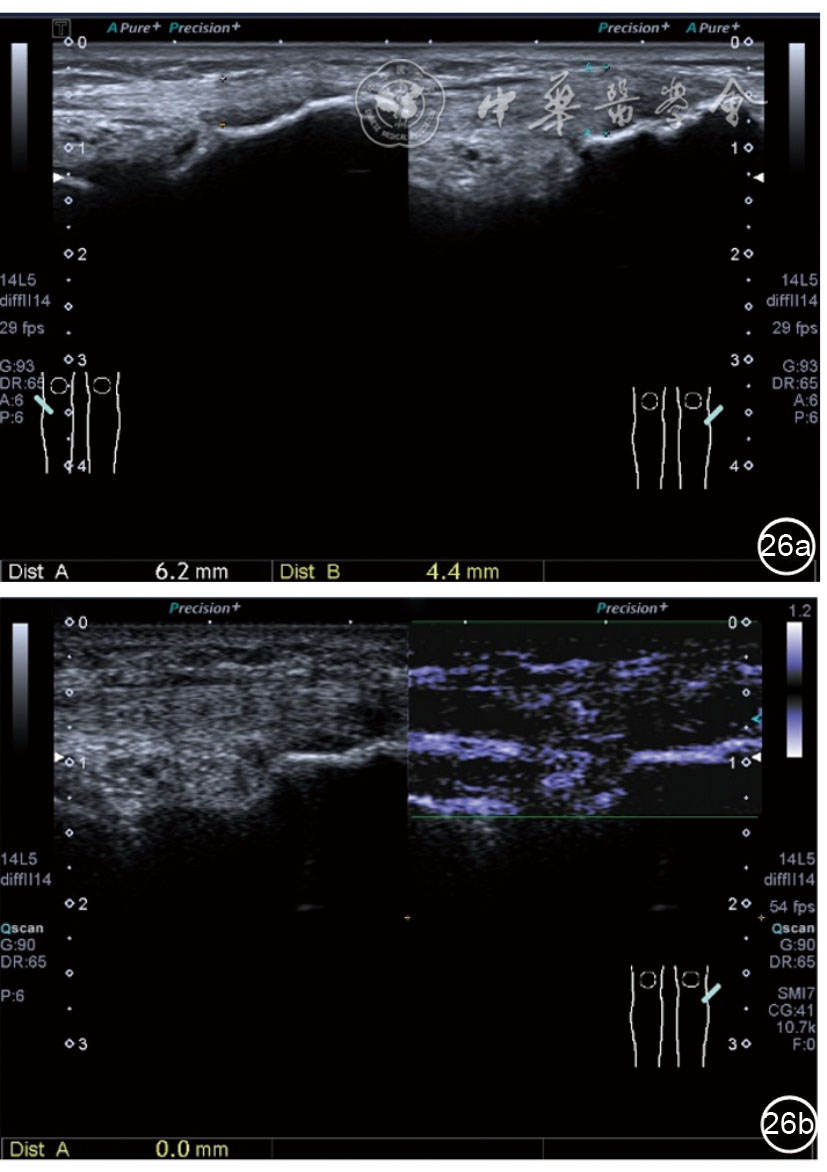

髂胫束的最佳显示切面为长轴切面,采用高频探头,扫查深度<3 cm。超声表现胫骨附着点处骨皮质不规则,髂胫束增厚,回声减低,其周围组织水肿,血流增加(图26)。股骨髁部肿胀、增厚,回声减低,超声触诊可能诱发股骨外侧髁处的疼痛。部分患者可见髂胫束滑囊扩张,内为无回声积液(图27)。

图26 超声图像显示胫骨附着点处骨皮质不规则,髂胫束增厚,回声减低,其周围组织水肿,血流增加

图27 超声图像显示股骨髁部肿胀、增厚,回声减低,部分患者可见髂胫束滑囊扩张